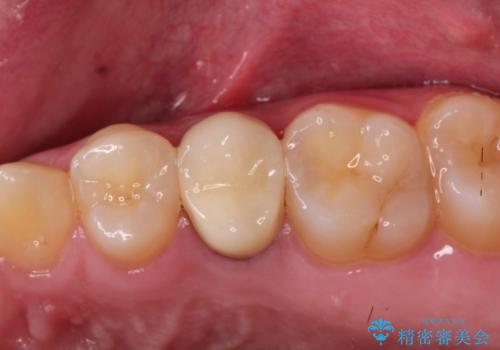

発見の難しい虫歯。根管治療から被せもの治療

- 定期検診にて被せものと歯との隙間に虫歯を発見した患者様です。

根管治療から被せもの治療(ベレッツァ)まで行いました。(根管治療は林院長に依頼)

妥協せずにすべての治療を行うことで最終的な被せものの適合を高める事ができます。